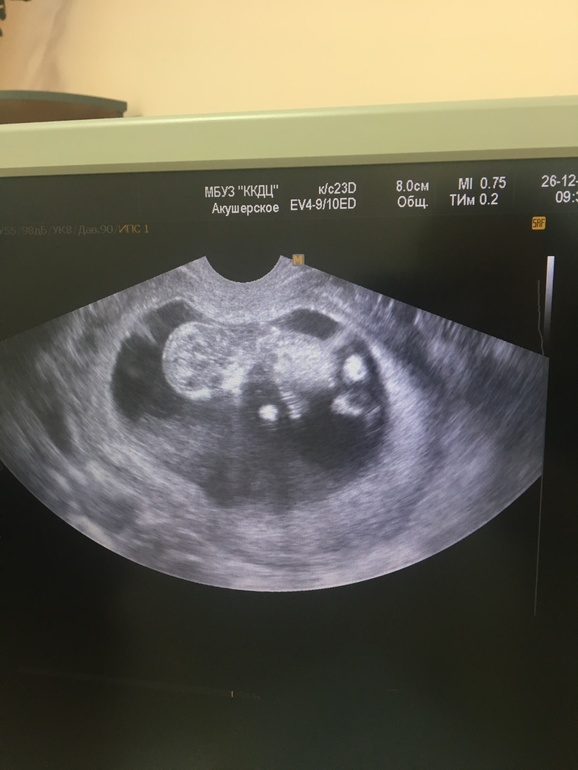

Наш первый скрининг

Результаты: УЗИ, КТГ, доплера, скринингаУуухх... сегодня прошла свой первый в жизни скрининг!!! Беременность к слову уже 4... было 3 потери. С утра встала а у меня коричневые выделения... но я без паники. Я лежала на сохранении 2 недели. Почти 3 недели мазало. Одна маленькая гематома так и осталась. Конечно когда я легла на кушетку, думала сердце мое выскочет 😱 слава богу с малышом все в норме. Все размерчики соответствуют нормам и срокам))) за отдельную плату можно попросить, что бы посмотрели пол) я так переживала, что даже забыла 😂 они даже фото не дают, но видя как меня трясёт, экран повернули )) по ходу малышки прячет, что там у него между ножек)) но может увидит кто там у нас?)) )